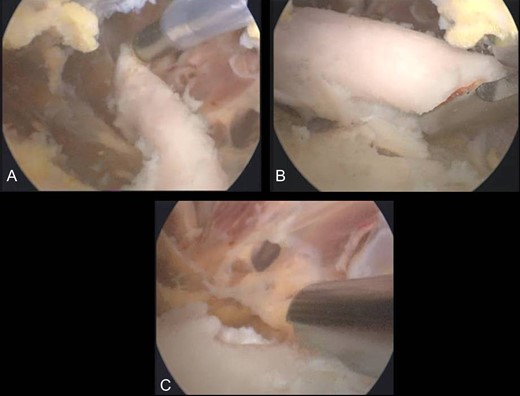

X-rays revealed an extra-articular mass at the medial aspect of the distal femur (Fig. 1A). Magnetic resonance imaging (MRI) confirmed the radiograph findings and no meniscal and ligament rupture or chondral defects were revealed. These characteristics were consistent with osteochondroma (Fig. 1B). Under general anesthesia, a standard antero-lateral portal used to access arthroscopically the knee. Cartilage surface, cruciate ligaments and menisci were normal. The osteochondroma was located extra-articularly, at the medial supracondylar side of the distal femur. Through a supero-medial portal and by perforating the capsule and a part of a medialis vastus muscle, the extra-articular lesion was reached arthroscopically (Fig. 2A). With an osteotome, the lesion was resected and removed with a grasper through the supero-medial portal (Fig. 2B). The remaining bony surface was abraded by a motorized shaver (Fig. 2C). The exostosis had maximum dimensions 3.1 × 2.5 cm. Histopathological examination confirmed the osteochondroma diagnosis.

(A) Arthroscopical view of the extra-articular knee osteochondroma, (B) Arthroscopic excision of the osteochondroma, C. Abrasion of the remaining bony surface.